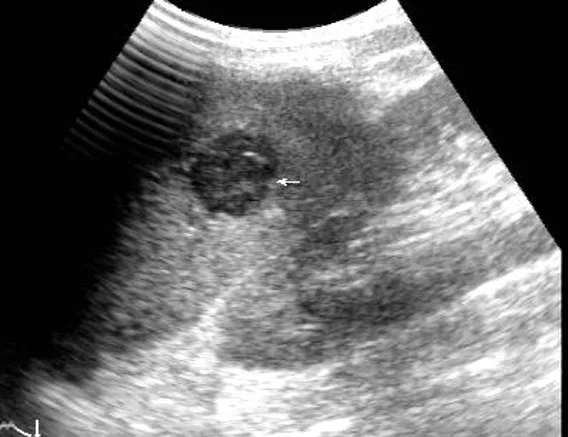

灰阶超声,脾破裂,显示脾实质内见低回声不均匀区,边界不规则(箭头所示) 。